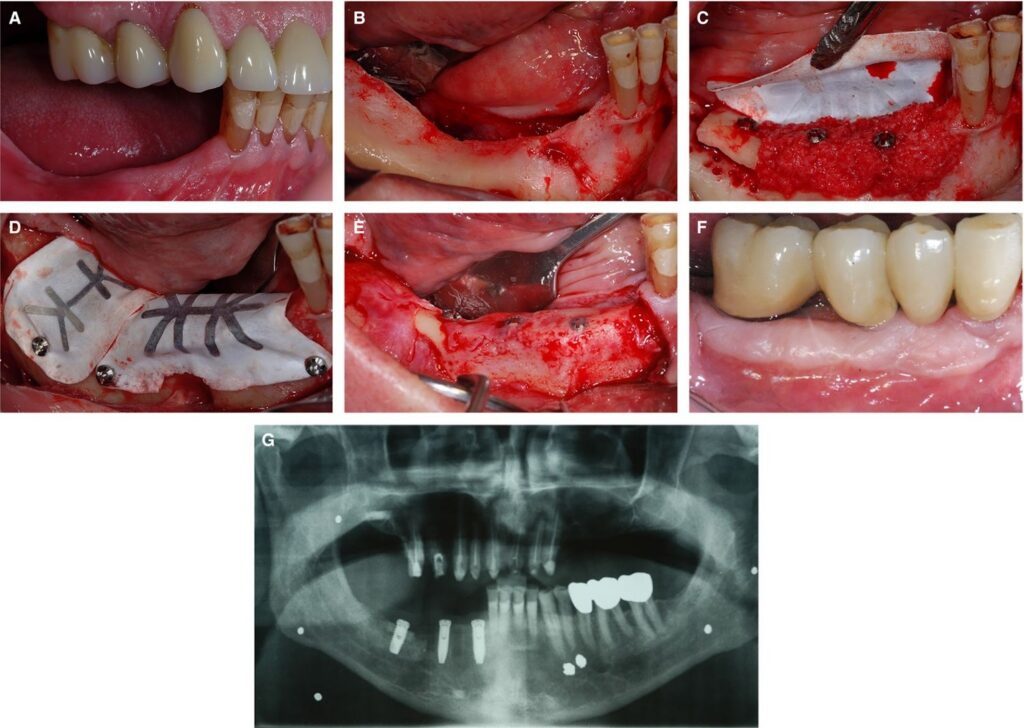

sursa foto: onlinelibrary.wiley.com